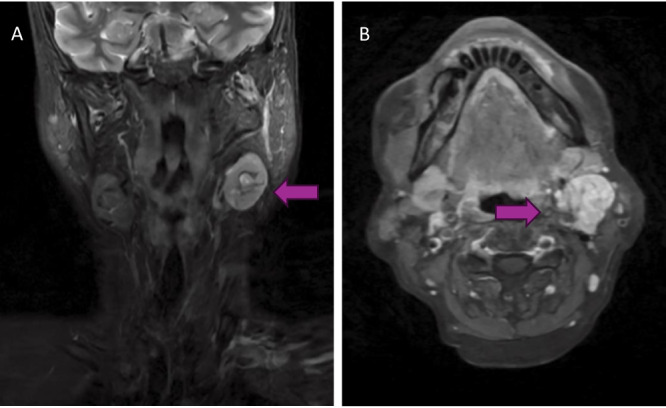

Objective: Mucoepidermoid carcinoma of unknown primary (MEC-UP) in the head and neck is a rare presentation of the most common salivary gland cancer. Cancers of unknown primary sites often have poorer prognoses than similar cancers with known primary. Few cases of MEC-UP have been reported; therefore, the objective of this report is an overview of the diagnosis and management of MEC-UP.

Methods: We present two patients with low-grade MEC-UP at a high-volume tertiary care institution in Ontario, and a database search returning 1560 citations of which five studies with seven MEC-UP cases were identified.

Results: Review of the limited cases suggest many clinicians use positron emission tomography-computed tomography (PET-CT) in addition to panendoscopy and targeted biopsies with consideration for diagnostic tonsillectomy in diagnostic work-up.

Conclusion: Like other salivary gland cancers, primary therapeutic surgical resection is recommended with low threshold for adjuvant radiotherapy to regions at high risk for harbouring the primary malignancy, especially in cases of high-grade histopathology.